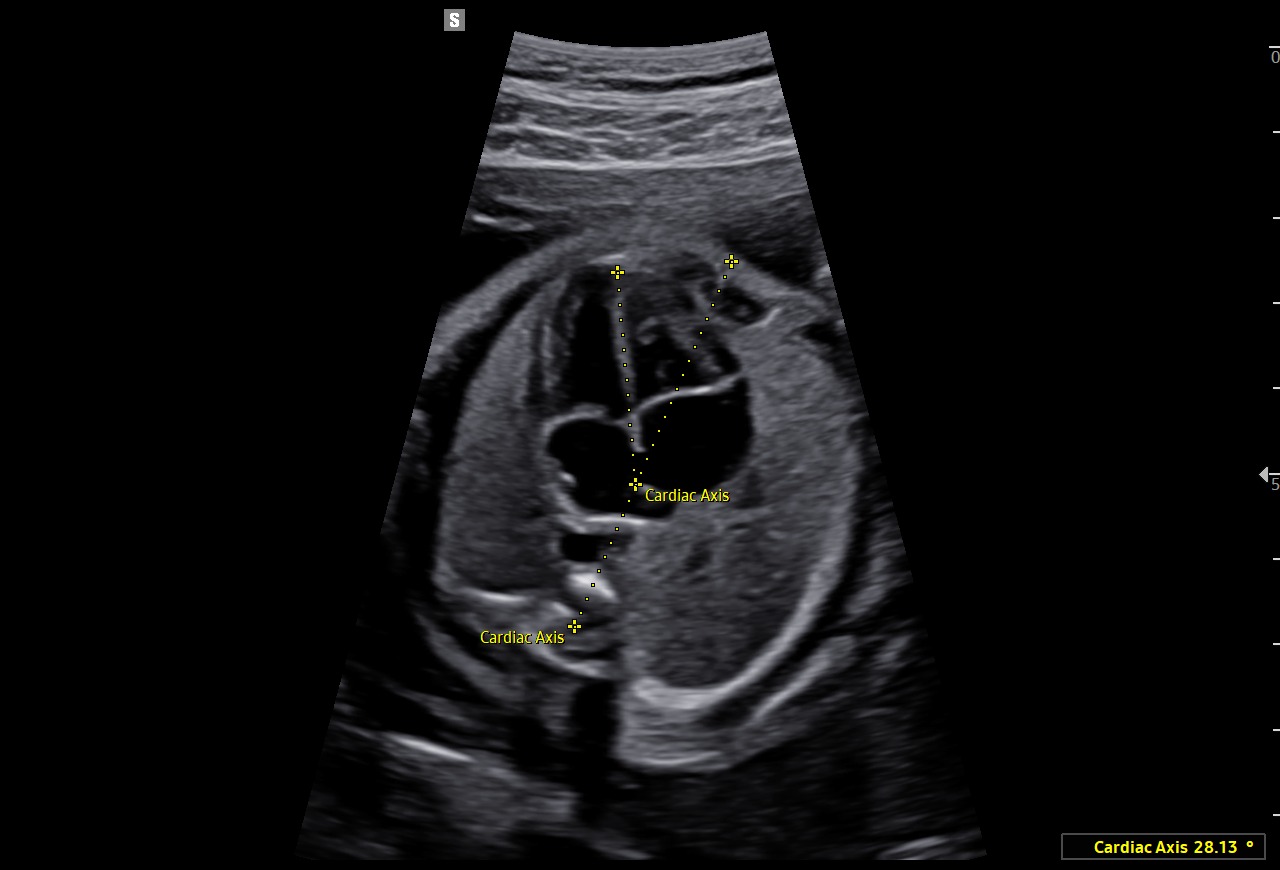

L’outil HeartAssist™, basé sur la reconnaissance d’images, permet d’identifier les structures de l’image échographique afin de réaliser automatiquement les mesures nécessaires à l’analyse du cœur fœtal. Il génère ensuite des résultats précis, ainsi que le tracé des courbes de normalité.